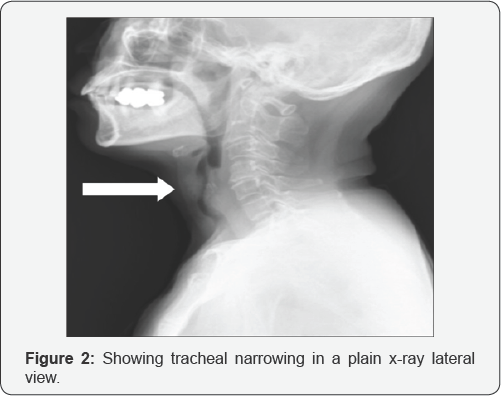

Neck X-Ray

The anteroposterior airway is superb for examining the glottic and subglottic areas. Cross-sectional imaging also adequately shows the airway. Configuration of the airway on axial or transverse images varies depending on the level of the image. At the level of the epiglottis and aryepiglottic folds, the airway is elliptic. Approaching the false cords, the airway narrows and assumes a teardrop shape. The airway becomes elliptic at the true cords. Below the cricoid cartilage, the airway appears circular. The posterior membrane of the trachea may posteriorly flatten, and the normal esophagus occasionally indents the airway silhouette [17] (Figure 2).